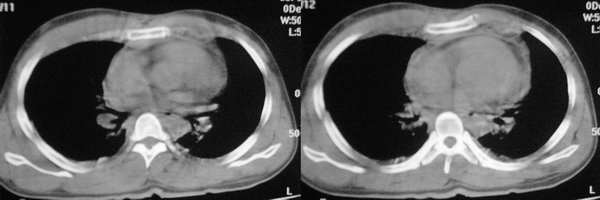

ssl1_1医生没有提供肺窗,从纵隔窗上看来似乎是右上纵隔增宽,但仔细观察发现病变边缘清楚锐利,右上叶支气管进入病灶内,病灶内可以见到残余气体密度影,所以必须要想到上叶肺不张的可能。在胸部外伤时,肺不张的发生原因是非常多而且复杂的,如支气管的断裂、管腔内血块或异物的阻塞、胸廓损伤导致呼吸肌无力、体位因素、脱水导致痰液不易咳出、胸腔积液的压迫等。心包和双侧胸腔均可见少量液体影,密度较高,应该考虑为少量积血。

该病例认为心包积液>纵隔血肿可能,其理由有以下几点:

3、主动脉弓以下大血管及心脏周围见环形低密度影,而主动脉弓以上大血管周边未见环形影。

5、复习了解剖后,可以看出该病例的低密度影,始终围绕大血管及心脏,而大血管以血管未见明显低密度影。

看了12,13楼的分析受益非浅,肺窗右肺上叶不张.左下肺挫伤.